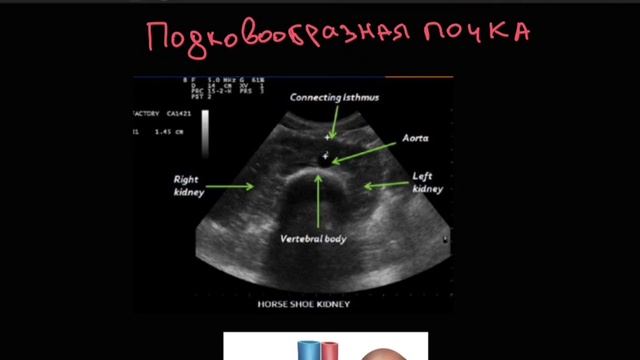

Агенезия почек. Подковообразная почка. Duplex collecting system. смотреть онлайн

Агенезия почек. Подковообразная почка. Duplex collecting system.